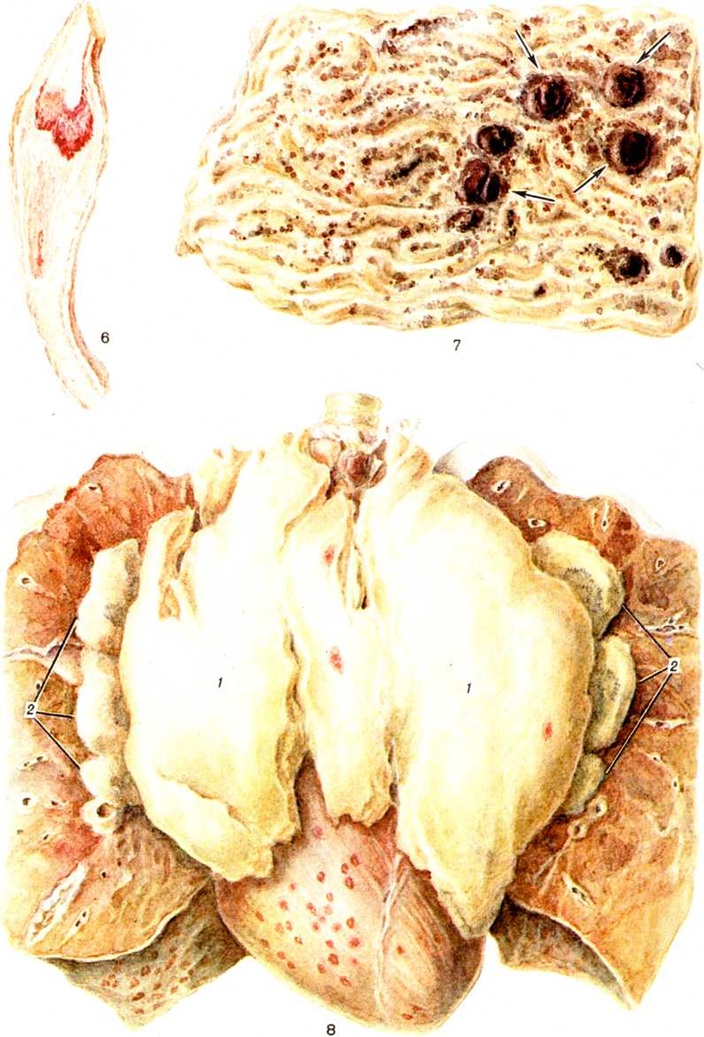

В костном мозге, по данным трепанобиопсии, на первых стадиях заболевания скопления бластных клеток являются очаговыми, в достаточном количестве обнаруживаются элементы деятельного костного мозга. Нередко наблюдаются острые расстройства кровообращения, участки гипоплазии, могут обнаруживаться некрозы. Прогрессирование заболевания характеризуется увеличением числа и размеров лейкозных разрастаний, их слиянием, а затем диффузной инфильтрацией ткани костного мозга. Количество нормальных кроветворных клеток заметно уменьшается. Часто имеется инфильтрация надкостницы, возможно распространение процесса в окружающие мягкие ткани. Развитие лейкозных разрастаний сопровождается выраженным рассасыванием костной ткани, преимущественно по типу гладкой резорбции. Очень редко в этом процессе принимают участие остеокласты. Вследствие частичного, а местами и полного рассасывания костных балок происходит значительное расширение костномозговых полостей, истончение, а в некоторых участках разрушение кортикального слоя. В раннем детском возрасте резкие изменения наблюдаются в зоне энхондрального окостенения. При острых Лейкозы редко отмечается очаговое новообразование атипичной костной ткани, богатой остеоидом, разрастание фиброзной ткани. Наряду с мелкими фокусами некроза иногда возникают обширные инфарктообразные коагуляционные некрозы, определяемые макроскопически в виде жёлто-белых сухих участков; в окружности наблюдаются кровоизлияния, возможно скопление макрофагов (рисунок 1). В области лейкозных разрастаний нередко обнаруживается истончение и частичный распад ретикулярных волокон. Описаны наблюдения с очаговым или диффузным миелофиброзом, который чаще выявляется при миелобластном Лейкозы. В таких случаях при пункции обычно не удаётся получить костный мозг и для установления диагноза необходимо исследование материала трепанобиопсии.

Лейкозная инфильтрация ткани селезёнки и лимфатических, узлов сопровождается уменьшением размеров (рисунок 2) и числа фолликулов вплоть до полного их исчезновения. В селезёнке часто наблюдается инфильтрация трабекул с разволокнением стенок трабекулярных сосудов, с деформацией и сужением их просвета, имеются поля кровоизлияний. В лимфатических, узлах вначале возникают очаговые инфильтраты, которые по мере прогрессирования болезни увеличиваются в размерах, и поражение становится диффузным.

Острый миелобластный лейкоз в развёрнутой стадии болезни характеризуется выраженной лейкозной инфильтрацией костного мозга и других органов. В печени лейкозные разрастания локализуются в синусоидных капиллярах и в области портальных трактов. Аналогичное расположение инфильтратов имеется и при других более редких формах острого Лейкозы (монобластном, миеломонобластном, недифференцируемом, промиелоцитарном и другие), поэтому данный признак не может служить основанием для разграничения форм острого Лейкозы В лёгких лейкозная инфильтрация обычно выявляется по ходу межальвеолярных перегородок с выходом бластных клеток в просветы альвеол (рисунок 3), возможна локализация и в окружности бронхов, сосудов, междольковых перегородках. У детей при этой форме Лейкозы лейкозные разрастания в вилочковой железе располагаются в соединительнотканных прослойках, сдавливают дольки, что сопровождается увеличением количества аргирофильных волокон. У взрослых типично развитие множественных узлов в надкостнице плоских и трубчатых костей, почках, печени, половых железах, жировой клетчатке (подкожной, ретробульбарной, клетчатке большого сальника и малого таза), иногда в коже, конъюнктиве, твёрдой мозговой оболочке и костном мозге. В ряде случаев в области опухолевых узлов и системных поражений имеется зелёное окрашивание ткани (хлоролейкоз). Аналогичные изменения могут выявляться и при Лейкозы у детей.

При остром мегакариобластном лейкозе в костном мозге выявляется большое количество атипичных мегакариоцитов и мегакариобластов, которые диффузно рассеяны в ткани, а местами образуют скопления (рисунок 4). Такие же клетки в значительном количестве содержатся в ткани и синусах селезёнки, лимфатических, узлов, просветах мелких сосудов печени, лёгких и других органов.

При микроскопическом исследовании в костном мозге преобладают незрелые и зрелые клетки гранулоцитарного ряда (рисунок 5), соотношение которых может варьировать. По данным трепанобиопсий, в начальной стадии заболевания ещё в достаточном количестве сохраняются элементы эритропоэтического и мегакариоцитарного ряда. По мере прогрессирования процесса их число снижается, исчезают жировые клетки. Характерны глубокие изменения в строме в виде сочетания процессов деструкции с увеличением количества фибробластов, аргирофильных и иногда коллагеновых волокон. Изучение костного мозга методом трепанобиопсии в динамике свидетельствует о том, что миелофиброз постепенно нарастает и бывает более выражен у больных с повторными ремиссиями и обострениями заболевания. В отдельных случаях в костном мозге имеют место обширные очаги некроза; постоянно наблюдается выраженное рассасывание костной ткани. В селезёнке и лимфатических узлах в развёрнутой стадии болезни обнаруживается диффузная инфильтрация миелоидными элементами, атрофия лимфатической ткани. Лейкозное поражение селезёнки часто сопровождается выраженным в различной степени фиброзом красной пульпы, образованием полей склероза, что наряду с инфильтрацией и полнокровием является причиной увеличения её веса. Для хронический миелолейкоза характерна локализация лейкозных инфильтратов в печени по ходу синусоидных капилляров (рисунок 6), в лёгких — в области межальвеолярных перегородок. Нередко наблюдается инфильтрация стенок мелких бронхов, сосудов, плевры. Реже, чем при острых Лейкозы очаги лейкозной инфильтрации возникают в почках, мышце сердца, в стенках желудочно-кишечные тракта, в оболочках и веществе головного мозга, коже, железах внутренней секреции и других органах.

Микроскопически в костном мозге обнаруживается системное разрастание лимфоцитов. При обострении процесса наряду со зрелыми лимфоцитами выявляются пролимфоциты и лимфобласты. В костном мозге выделяют три типа инфильтрации: диффузную, диффузно-очаговую, очаговую. При первых двух типах инфильтрации расширенные полости костного мозга содержат значительное количество лимфоцитов, диффузно рассеянных в ткани или образующих наряду с этим компактные скопления (диффузно-очаговый тип). В отличие от других форм Лейкозы даже при массивной инфильтрации в костном мозге сохраняются небольшие очаги нормального кроветворения, не исчезают полностью жировые клетки. Для хронический лимфолейкоза характерно резкое рассасывание костной ткани и отсутствие признаков её новообразования. Данные прижизненного гистологический исследования костного мозга показывают, что очаговый тип инфильтрации наблюдается в ранние стадии заболевания. В отличие от лимфоидных узелков, выявляемых в норме в костном мозге, а также от реактивной нодулярной лимфоидной гиперплазии, сопутствующей ряду заболеваний, при хронический лимфолейкозе очаговые скопления лимфоцитов характеризуются довольно крупными размерами, лишены чётких границ, имеют тенденцию к слиянию, содержат наряду со зрелыми лимфоцитами пролимфоциты и лимфобласты. Разграничение этих изменений с метастазами в костный мозг лимфоцитарной лимфосаркомы ввиду сходности морфологический картины основывается на особенностях клинические, проявлений заболевания. При развёрнутой картине хронический лимфолейкоза в лимфатических, узлах обнаруживается диффузная инфильтрация ткани лимфоцитами с полным стиранием рисунка, которая может проникать через капсулу в окружающую жировую клетчатку. В селезёнке в некоторых случаях видны резко увеличенные в размерах фолликулы без центров размножения, сливающиеся друг с другом, однако чаще имеется полное стирание рисунка вследствие диффузной инфильтрации ткани лимфоцитами. Нередко встречаются поля склероза. В печени обширные скопления лимфатических, клеток располагаются главным образом в области портальных полей (рисунок 7), но могут встречаться и в синусоидных капиллярах. В зонах инфильтрации нередко имеет место разрастание аргирофильных и коллагеновых волокон. Часто наблюдается расширение желчных капилляров и застой желчи, дистрофия, частичный некробиоз и некроз гепатоцитов. В лёгких разрастания локализуются в стенках бронхов, что приводит к нарушению их дренажной функции и способствует развитию пневмоний. Могут наблюдаться участки массивной лейкозной инфильтрации ткани лёгкого. При микроскопии гнездные скопления лимфоцитов нередко обнаруживаются в строме почек, оболочках и мышце сердца, половых железах, жировой клетчатке и так далее. Очень редко встречается специфическая инфильтрация оболочек и вещества головного мозга. Частой находкой является скопление лимфоцитов в просветах сосудов различных органов, особенно при значительном лейкоцитозе. В отдельных случаях при обострении хронический лимфолейкоза возникают массивные опухолевые разрастания, исходящие главным образом из лимфатических, узлов. Опухолевые массы состоят из крупных недифференцированных клеток с уродливыми ядрами, нередко в них обнаруживаются участки некроза, кровоизлияния. Характерен резко выраженный инфильтрирующий рост.

При всех формах Лейкозы наиболее интенсивное подавление лейкозной инфильтрации наблюдается в костном мозге. При вскрытии костный мозг плоских костей очагово или на всем протяжении суховатый, серого или серо-жёлтого цвета, в нем имеются участки жировой ткани и тёмно-красные поля кровоизлияний. При микроскопическом исследовании количество клеток в костном мозге снижено, видны поля опустошения различной величины, состоящие из отёчной стромы с наличием макрофагов и единичных бластных клеток (рисунок 8), зоны геморрагического пропитывания. Лейкозные инфильтраты располагаются очагово, содержат много клеток в состоянии лизиса, пикноза, распада (рисунок 9). Могут встречаться очаги некроза, представленные распадающимися лейкозными клетками, а также участки тотального коагуляционного некроза ткани с одновременной гибелью стромы. Иногда видны гигантские клетки с уродливыми гиперхромными ядрами, появление которых связывают с дистрофическими изменениями бластных элементов. Такие же клетки иногда выявляются в других органах.

В стадии полной ремиссии имеет место выраженное в различной мере восстановление деятельной кроветворной ткани, однако все же нередко обнаруживаются бластные клетки в виде мелких скоплений или одиночно расположенных элементов. При острых, а также хронический Лейкозы протекающих с повторными ремиссиями, часто имеется заметное увеличение жировых клеток (рисунок 10); в связи с длительным применением кортикостероидов нарастают процессы резорбции костного вещества, отражением чего является резкое истончение, а местами полное разрушение костных балок (рисунок 10). Эти изменения наиболее выражены при острых Лейкозы у детей и могут сопровождаться образованием известковых метастазов.